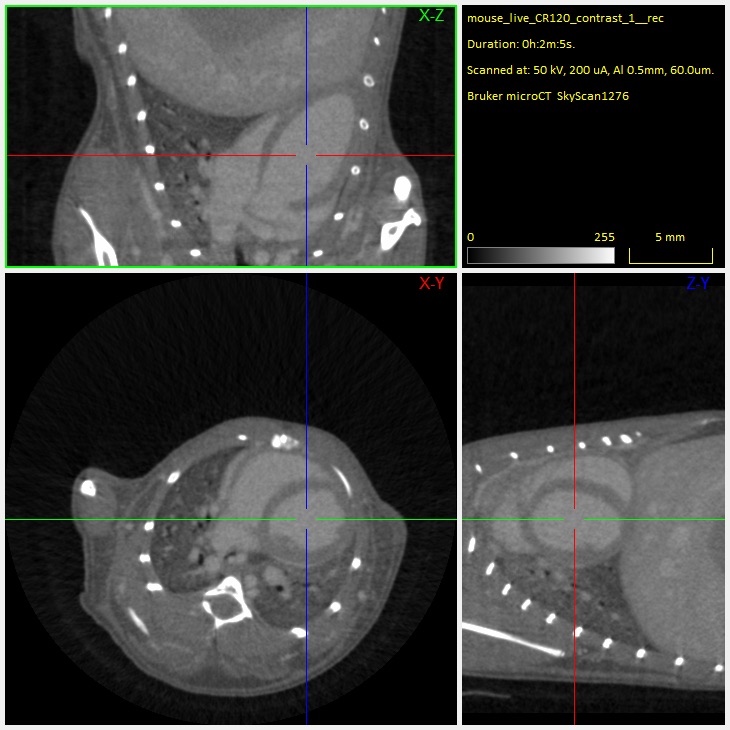

5. Orthogonal cross-sections through the mouse lung scannedin vivo, showing the blood vessels and large airways inside the lung.

6. Cross-sectional slices through a mouse body, scanned at 17um voxel size in vivo without contrast agent injection.